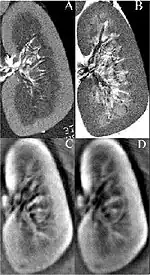

Fig. 1. Bottom: The first 3D thermoaoustic images of biologic tissue (lamb kidney). Top: MRIs of the same kidney.

Thermoacoustic imaging was originally proposed by Theodore Bowen in 1981 as a strategy for studying the absorption properties of human tissue using virtually any kind of electromagnetic radiation.[1] But Alexander Graham Bell first reported the physical principle upon which thermoacoustic imaging is based a century earlier.[2] He observed that audible sound could be created by illuminating an intermittent beam of sunlight onto a rubber sheet. Shortly after Bowen's work was published, other researchers proposed methodology for thermoacoustic imaging using microwaves.[3] In 1994 researchers used an infrared laser to produce the first thermoacoustic images of near-infrared optical absorption in a tissue-mimicking phantom, albeit in two dimensions (2D).[4] In 1995 other researchers formulated a general reconstruction algorithm by which 2D thermoacoustic images could be computed from their "projections," i.e. thermoacoustic computed tomography (TCT).[5] By 1998 researchers at Indiana University Medical Center[6] extended TCT to 3D and employed pulsed microwaves to produce the first fully three-dimensional (3D) thermoacoustic images of biologic tissue [an excised lamb kidney (Fig. 1)].[7] The following year they created the first fully 3D thermoacoustic images of cancer in the human breast, again using pulsed microwaves (Fig. 2).[8] Since that time, thermoacoustic imaging has gained widespread popularity in research institutions worldwide.[9][10][11][12][13][14][15] As of 2008, three companies were developing commercial thermoacoustic imaging systems – Seno Medical,[16] Endra, Inc.[17] and OptoSonics, Inc.[18]